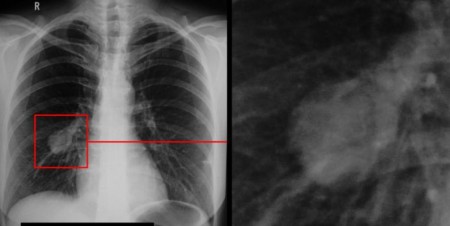

Красноярские медики запатентовали новый метод диагностики рака лёгких

Специалисты Центра ядерной медицины Федерального Сибирского научно-клинического центра ФМБА России разработали и запатентовали инновационный способ диагностики рака лёгких. Новый метод позволит выявлять заболевание на ранних стадиях и обнаруживать даже мельчайшие метастазы.